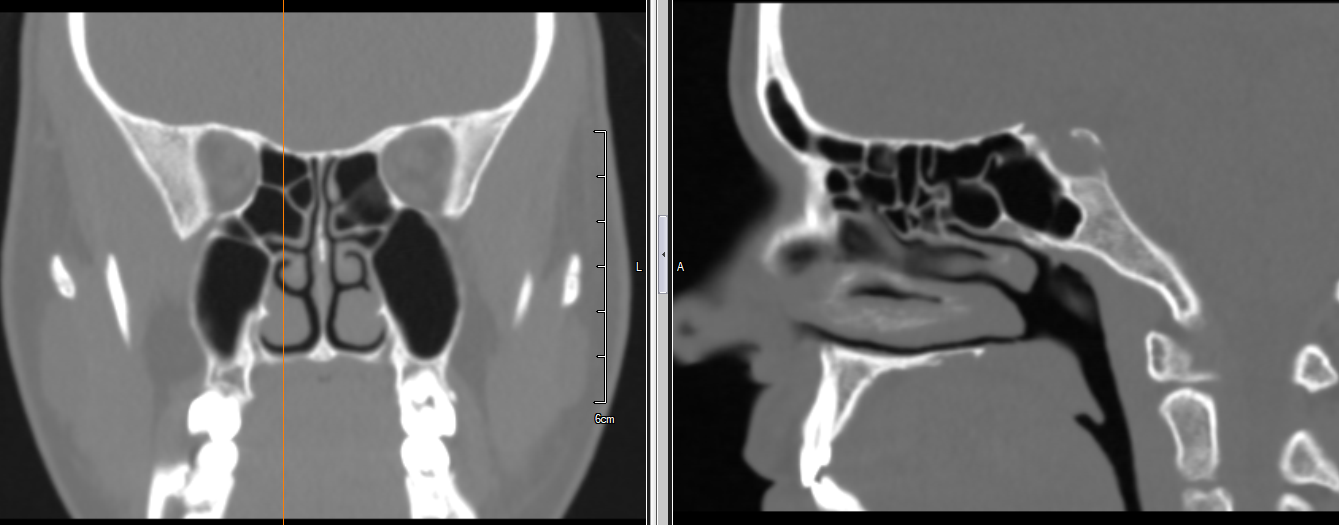

När du har fått diagnosen kronisk bihåleinflammation och är planerad för operation behöver du genomgå en förundersökning. Förundersökningen sker på vårt privata sjukhus i Charlottenlund, där läkaren undersöker dina bihålor med en kort endoskopisk undersökning och en granskning av datortomografin av dina bihålor.

Den endoskopiska undersökningen kan ofta fastställa orsaken till din kroniska bihåleinflammation. Beror det till exempel på näspolyper, stora näsmusslor, en sned nässkiljevägg eller något annat? Läkaren kan enkelt fastställa detta med hjälp av den endoskopiska undersökningen och datortomografin. Om operation krävs för näspolyper, stora näsmusslor eller en sned nässkiljevägg kommer detta att överenskommas i förväg.

Studien visar också om det, på grund av anatomin, kommer att finnas svårigheter att komma åt bihålorna under operationen.

Operationen syftar till att skapa permanent dränage från bihålorna och ner i näsan genom att expandera det naturliga dränaget från bihålorna. Den utförs genom näsborrarna och med hjälp av avancerad 3D-datornavigeringsutrustning, den så kallade CAS FESS-tekniken. Eftersom inga två patienter är likadana kan sättet på vilket dränage skapas skilja sig från patient till patient. Ingreppet bestäms av kirurgen under den förberedande undersökningen.